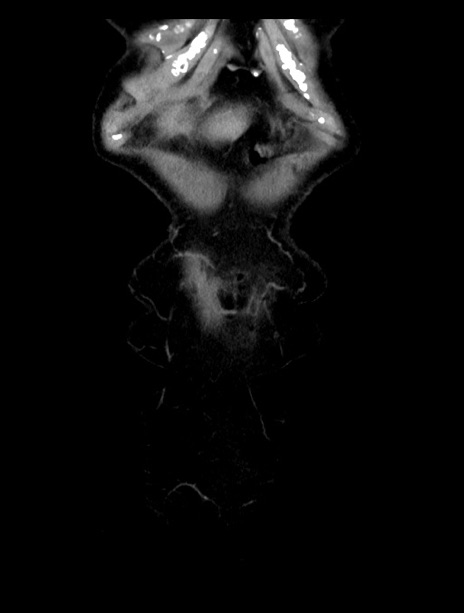

症例23(冠状断像)

【症例】70歳代女性

【主訴】下腹部痛・嘔吐

【現病歴】2日前より腹痛あり。昨日嘔吐あり。症状改善しないため来院。

【既往歴】胃GISTに対して胃部分切除後。

【身体所見】BT 37.1℃、BP 128/77mmHg、腹部:平坦・軟、下腹部に圧痛あり。

【データ】WBC 10200、CRP 0.31